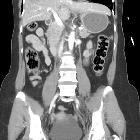

CT

Direct discontinuity of the hemidiaphragm may be seen with or without intrathoracic herniation of abdominal contents. The stomach and colon are the most common viscera to herniate on the left side and the liver is the most common viscus to herniate on the right side.

Other signs of diaphragmatic rupture include:

- the collar sign (or hourglass sign): a waist-like constriction of the herniating hollow viscus from the abdomen into the chest at the site of the diaphragmatic tear, which is classical for diaphragmatic rupture

- the dependent viscera sign: when a patient with a ruptured diaphragm lies supine at CT examination, the herniated viscera (bowel or solid organs) are no longer supported posteriorly by the injured diaphragm and fall to a dependent position against the posterior ribs

- segmental non-recognition of the diaphragm

- focal diaphragmatic thickening

- thoracic fluid abutting the abdominal viscera